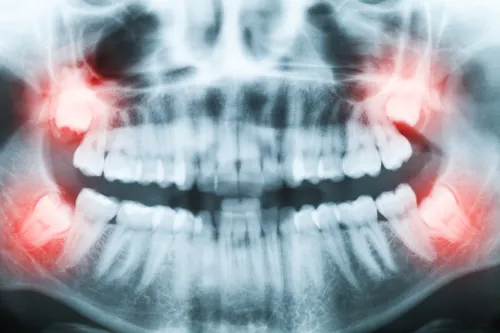

Zjawisko Godona: dlaczego ważna jest równowaga między górnymi i dolnymi zębami?

Zjawisko Godona to problem, który może wystąpić, gdy usuniemy tylko jeden ząb mądrości, nie usuwając jego odpowiednika w przeciwległym łuku (antagonisty). Na przykład, jeśli usuniemy dolną ósemkę, a górna pozostanie, ząb górny, pozbawiony kontaktu z dolnym, zacznie się wysuwać z kości (ekstruzja). To zaburza równowagę zgryzową, prowadzi do nieprawidłowych kontaktów podczas żucia, może powodować przeciążenia, a nawet problemy ze stawem skroniowo-żuchwowym. Dlatego często zaleca się usunięcie obu zębów mądrości z danej strony, aby zapobiec temu zjawisku i utrzymać prawidłową równowagę w zgryzie.